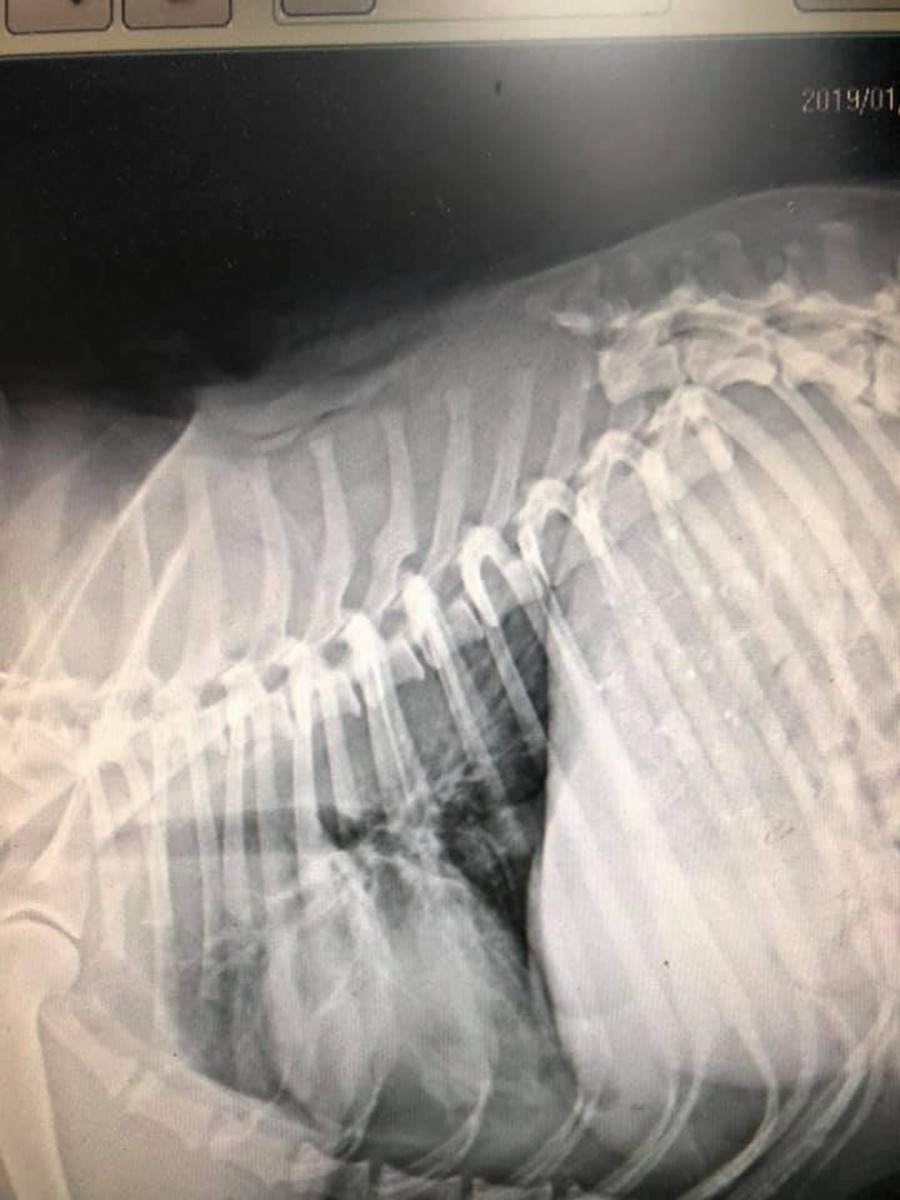

台灣新竹芎林有隻小白狗在上(1)月17日遇上車禍,重傷命危。好心人把牠救到動物醫院,當時牠全身擦傷,口吐鮮血,牙齦因失血過多而沒有血色,意識模糊,身體冰冷一直發抖。由於牠脊椎斷裂,醫生也認為撐不下去。